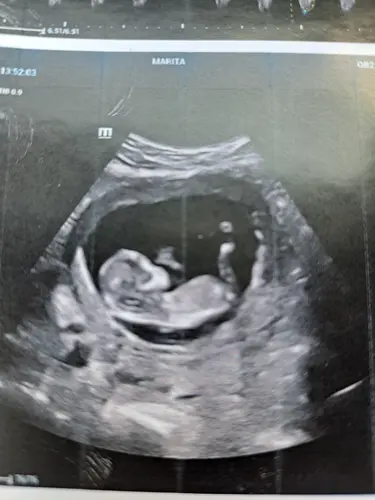

Gisteren echo en nip test gehad 12w6. Wat denken jullie?😍

Wat denken jullie? Echo op 12w5d.

12 weken echo wat denken jullie 😍